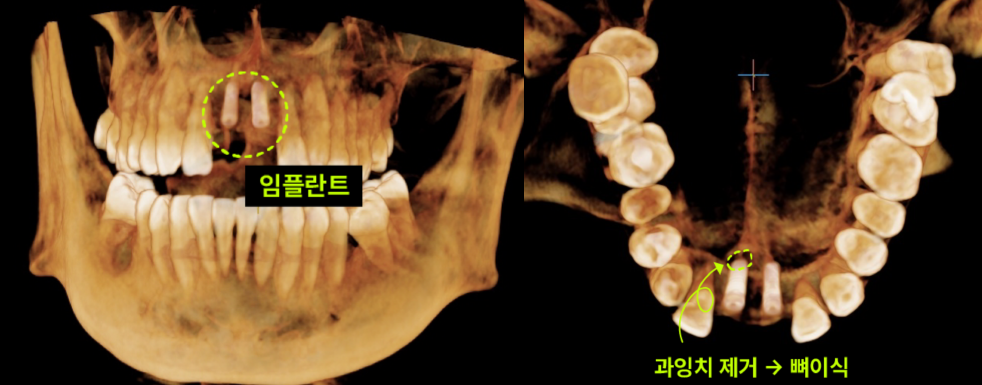

과잉치 제거와 임플란트, 한 번에 해결!✨ 이번 케이스의 핵심은 과잉치 발치와 임플란트 식립을 동시에 진행한 것입니다.

최소 침습으로 동시에 해결! 과잉치 제거&임플란트 이백점치과에서는 환자분의 부담을 줄이면서도 최상의 결과를 위해, 과잉치 제거와 동시에 임플란트 식립까지 한번에 진행하기로 치료 계획을 세웠습니다. 1. 과잉치 제거 : 입천장 잇몸을 조심스럽게 열고 잇몸 뼈를 최소한으로 삭제하여 과잉치를 안전하게 발치했습니다. 2. 동시 임플란트 식립 : 과잉치 제거 후 바로 그 부위에 임플란트를 정교하게 식립하여 수술 횟수와 치료 기간을 단축했습니다.

최소 침습으로 동시에 해결! 과잉치 제거 & 임플란트 식립 이백점치과에서는 환자분의 부담을 줄이면서도 최상의 결과를 위해, 과잉치 제거와 동시에 임플란트 식립까지 한 번에 진행하기로 치료 계획을 세웠습니다. 1. 과잉치 제거: 입천장 잇몸을 조심스럽게 열고 잇몸 뼈를 최소한으로 삭제하여 과잉치를 안전하게 발치했습니다. 2. 동시 임플란트 식립: 과잉치 제거 후 바로 그 부위에 임플란트를 정교하게 식립하여 수술 횟수와 치료 기간을 단축했습니다.